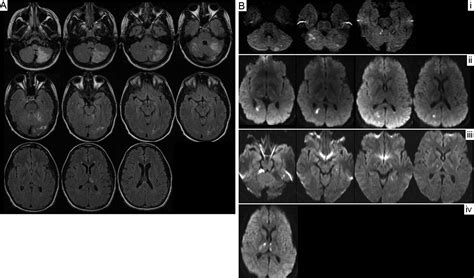

• Bone Infections (Osteomyelitis): An acute infection within the bone can cause inflammation and structural changes that appear on scans.

• Acute Bone Infarction: This occurs when the blood supply to a portion of the bone is suddenly cut off, leading to tissue death.

A radiologist interprets images in a vacuum of your daily life—they look only at the pixels on the screen. Your physician, however, looks at the whole picture. For example, if a 20-year-old athlete reports sharp pain in their shin after a high-intensity workout and the scan shows an acute osseous abnormality, the physician will almost certainly diagnose a stress reaction or stress fracture. Conversely, if a 70-year-old with a history of cancer reports vague bone pain in the same area, that same imaging finding might prompt an urgent workup to rule out a metastatic lesion.